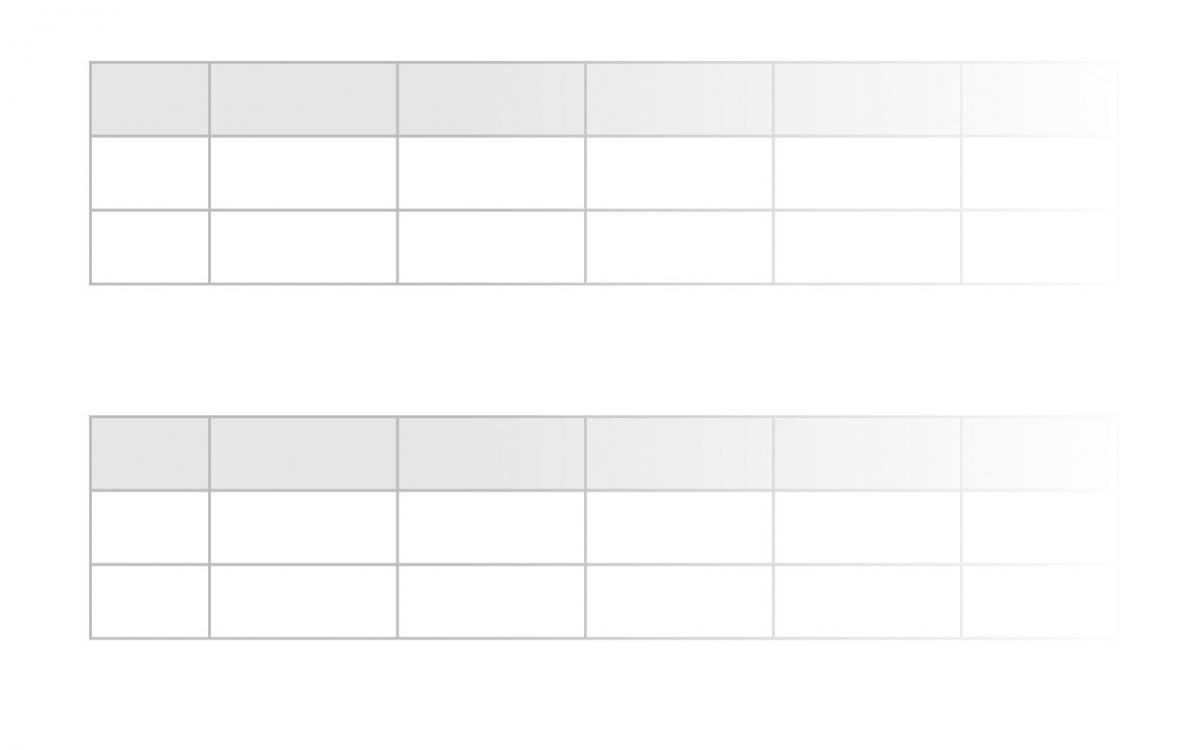

Mehr …Mikrobiologische Verfahren erlauben heute den Zugang zu Informationen, die klassischen Untersuchungsmethoden bisher verwehrt geblieben sind.

Mikrobiologischer Test

Mikrobiologische Verfahren erlauben heute den Zugang zu Informationen, die klassischen Untersuchungsmethoden bisher verwehrt geblieben sind.

Der Aufwand dieser zusätzlichen diagnostische Bemühungen ist dann gerechtfertigt, wenn die gewonnene Information zu einer Verbesserung der Therapie führt, oder wenn damit unnötige Behandlungen vermieden werden können.